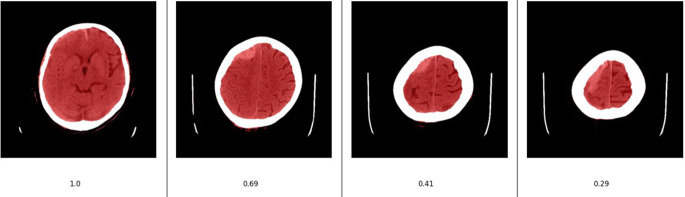

Methods: A convolutional neural network (CNN) was trained and validated to detect ICHs on DICOM images of cranial CT (CCT) scans, utilizing about 674,000 individually labeled slices. The CNN was then incorporated into a commercial AI engine and seamlessly integrated into three pilot centers in Germany. A real-world test-dataset was extracted and manually annotated by two experienced experts. The performance of the AI algorithm against the two raters was assessed and compared to the inter-rater agreement. The overall time ranging from data acquisition to the delivery of the AI results was analyzed.

Abstract Image